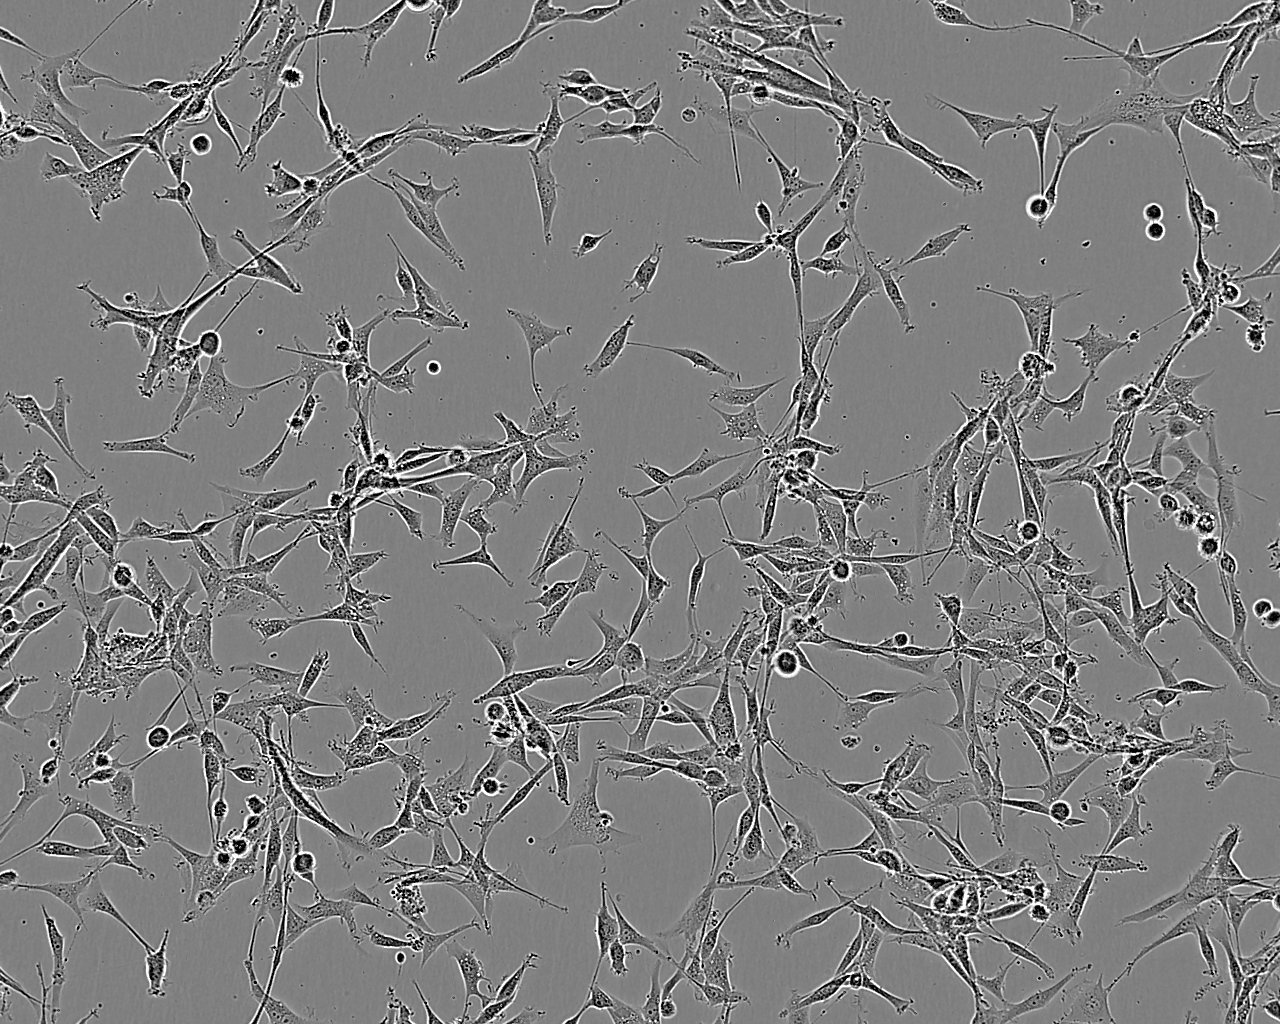

细胞形态:上皮细胞样

细胞生长:贴壁